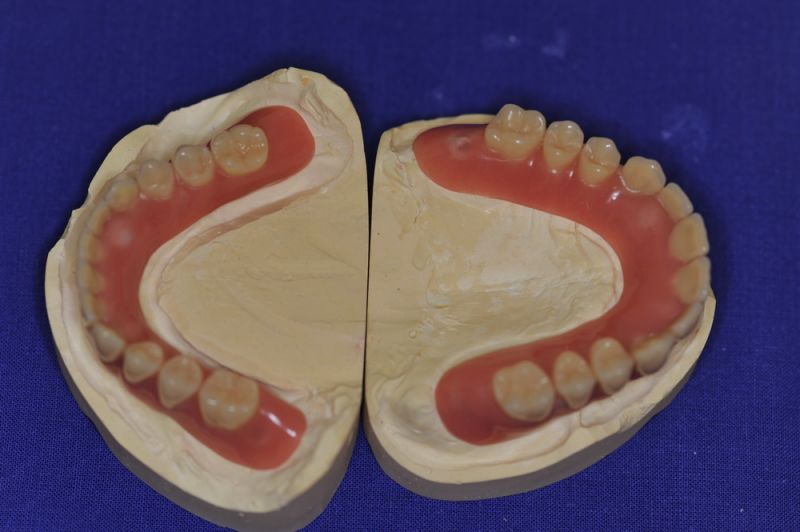

Patient aus der Region Eckernförde erhält neue implantatgestützte Cover Denture Prothesen

Der Patient erhält heute eine neue implantatgetragene Prothesenrekonstruktion im Ober- und Unterkiefer.

Die Neuversorgung war weniger einem ausgewechselten Implantat geschuldet, als der Langjährigkeit der bestehenden Arbeit und der damit verbundenen Materialermüdung.

Die Arbeit wurde im Jahr 2005 inkorporiert, war damit also 10 Jahre in Funktion und wurde mehrfach umfangreich überarbeitet und instandgehalten.